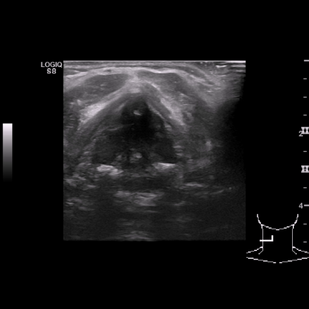

• Обложка: 1.1 Истинные доброкачественные узлы в поперечном сечении